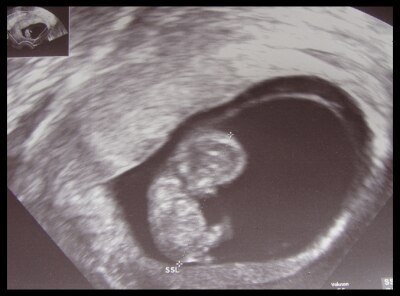

,sind wir trotz intensiven trauern glücklicherweiße wieder schwanger geworden. bisher scheint diese schwangerschaft intakt zu sein- herzchen schlägt kräftig und es wächst und zabbelt fleißig herrum...

Na, dann drücke ich Dir und Deiner Familie von ganz Herzem die Daumen für diese SS und diesen süßen Krümel auf dem US-Bild.